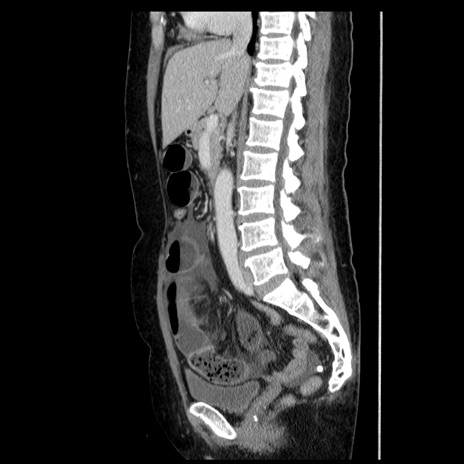

症例6(矢状断像)

症例